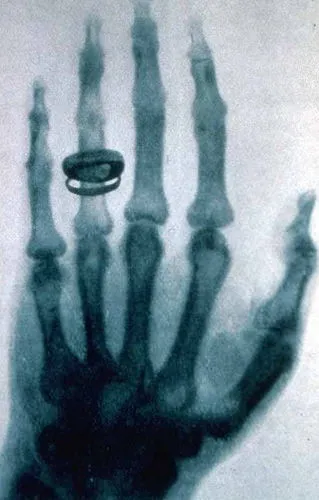

दुनिया का पहला एक्स-रे फोटो

रोंटगन ने अपनी खोज का सबसे बड़ा सबूत तब पेश किया जब उन्होंने 22 दिसंबर 1895 को अपनी पत्नी अन्ना बर्था के हाथ का रेडियोग्राफ लिया। उन्होंने अपनी पत्नी का हाथ फोटोग्राफिक प्लेट पर रखा और उस पर से एक्स-रे को गुजारा।

जब प्लेट को डेवलप किया गया, तो वहां उनकी पत्नी के हाथ की हड्डियां और उनकी शादी की अंगूठी साफ दिखाई दे रही थी, मानो अंगूठी हवा में तैर रही हो।

यह इतिहास का पहला मानव एक्स-रे फोटो था। इस भूतिया इमेज को देखकर अन्ना बर्था चिल्ला उठी थीं, "मैंने अपनी मौत देख ली!" यह एक ऐसा पल था जिसने सदियों पुराने मेडिकल रहस्य को खोल दिया। अब डॉक्टर बिना चीरफाड़ किए इंसान के शरीर के अंदर देख सकते थे।